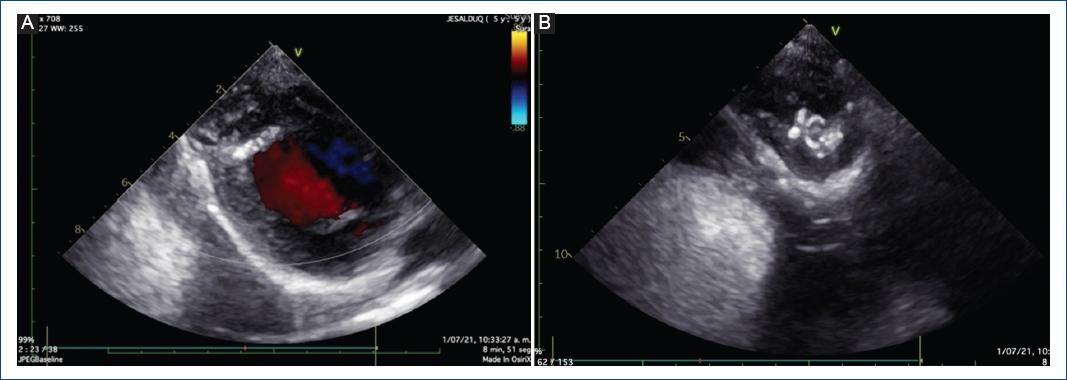

Se realizó ecocardiografía de control, en la cual se evidenció el aneurisma excluido (Fig. 3). Sin embargo, al año de seguimiento, mediante ecocardiografía se evidenció un defecto residual en el parche, con dos fugas residuales de 1.5 y 2.5 mm, con cortocircuito bidireccional en la punta del ventrículo izquierdo hacia la bolsa residual pericárdica, con función ventricular sistólica conservada, discinesia e hipocinesia de la punta ventricular izquierda (en el sitio del parche quirúrgico) (Fig. 4).

Figura 4 Ecocardiografía transtorácica. A: eje corto paraesternal, con evidencia de fuga residual en el parche de pericardio. B: eje apical de cuatro cámaras mirando al ápex, con evidencia de fuga residual.